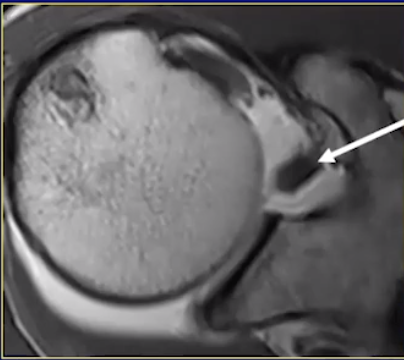

Superior glenohumeral ligament

• Image showing its attachment from the anterior superoir labrum

• Then swings toward the coracoid process where its joints the coracohumeral ligament

• Then continues to its attachment near the bicipital groove

• There are other less common morphology like common origin with MGHL